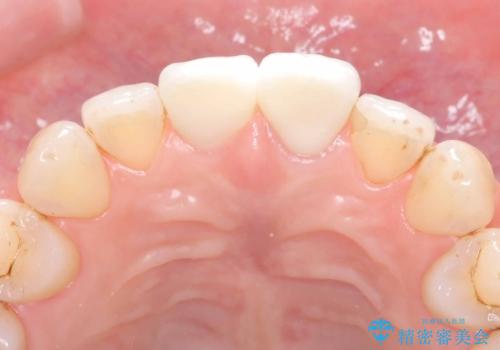

精密根管治療を行い、その後オールセラミッククラウンで審美的に修復しています。あわせてホワイトニングとエアフローによるクリーニングも行い、自然で美しい仕上がりとなりました。

他院で抜歯と診断された歯が、当院での治療により2本とも保存でき、見た目もきれいに仕上がりました。患者様にも大変ご満足いただけました。